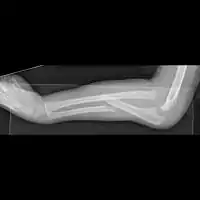

Monteggia fracture dislocation

Monteggia fracture

Monteggia fractures may be managed conservatively in children with closed reduction (resetting and casting), but due to high risk of displacement causing malunion, open reduction internal fixation is typically performed.[4]

Osteosynthesis (open reduction and internal fixation) of the ulnar shaft is considered the standard of care in adults. It promotes stability of the radial head dislocation and allows very early mobilisation to prevent stiffness. The elbow joint is particularly susceptible to loss of motion.